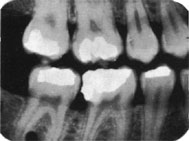

Radiografía de aleta mordible (Bite-Wing)

La técnica tiene ventajas con respecto a la radiografía periapical, debido que  reduce el tiempo de exposición a la radiación  y disminuye los costos y honorarios.

La cabeza del paciente se coloca de manera que el plano de oclusión quede paralelo al del piso. El rayo central se dirige al punto de contacto de los dientes superiores con los dientes inferiores y paralelo a sus superficies proximales, con el tubo formando un ángulo de 5 a 10º por encima del plano horizontal.

Para los dientes posteriores es deseable tomar dos vistas de cada lado:

• una en la que la película  se coloca más atrás para incluir el espacio inter-proximal  entre el segundo y el tercer molar,

• y la otra lo bastante adelante como para tomar la cara distal del canino. Solo necesita cuatro películas para el diagnóstico de caries en todos los sectores posteriores.

Debe tener en cuenta el tiempo de exposición y  el kilovoltaje  del equipo radiográfico, como la sensibilidad de la película radiográfica.

A modo de ejemplo con una película tipo  Speed y un  kilovoltaje de 65;  el tiempo de exposición es de 0.8 segundos en zona de molares. En Premolares y Caninos 0.7; y en Incisivos 0.6 segundos.